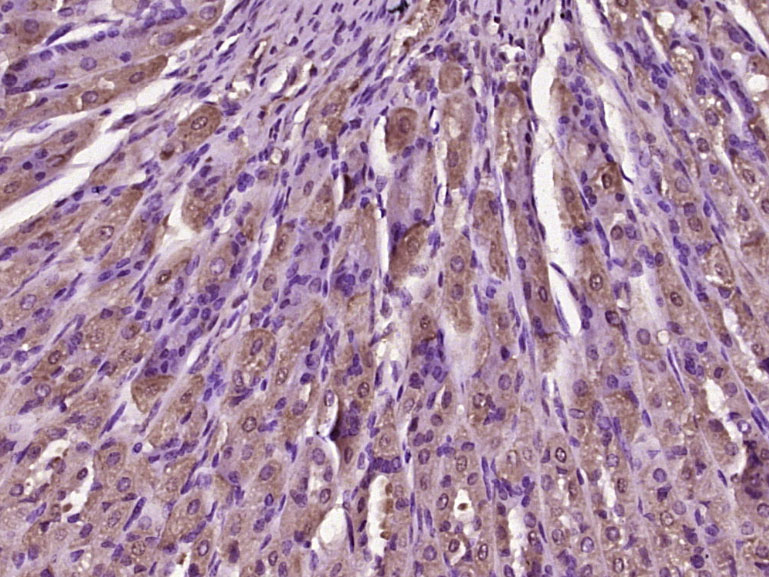

產(chǎn)品圖片

Paraformaldehyde-fixed, paraffin embedded (mouse stomach tissue); Antigen retrieval by boiling in sodium citrate buffer (pH6.0) for 15min; Block endogenous peroxidase by 3% hydrogen peroxide for 20 minutes; Blocking buffer (normal goat serum) at 37°C for 30min; Antibody incubation with (TFF2) Polyclonal Antibody, Unconjugated (bs-23857R) at 1:400 overnight at 4°C, followed by operating according to SP Kit(Rabbit) (sp-0023) instructionsand DAB staining.